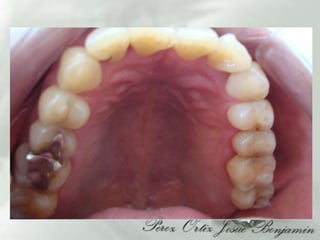

DIAGNOSTICOAparatos y sistemas:  Refiere :Antecedentes de Calculos Biliares , Intervencionquirugica aproximadamente hace 10 años    Bronquitis, aproximadamente hace 5 añosAntecedentes heredofamiliares 3 Hermanos con diabetes tipo II, Gingivitis Zona dientes anteriores inferioresLesiones cariosas grado I (24.25.27, 34)Restauraciones desajustadas (37,38,47,48,25, 26)  Oclusionismo  aproximadamente 15 años